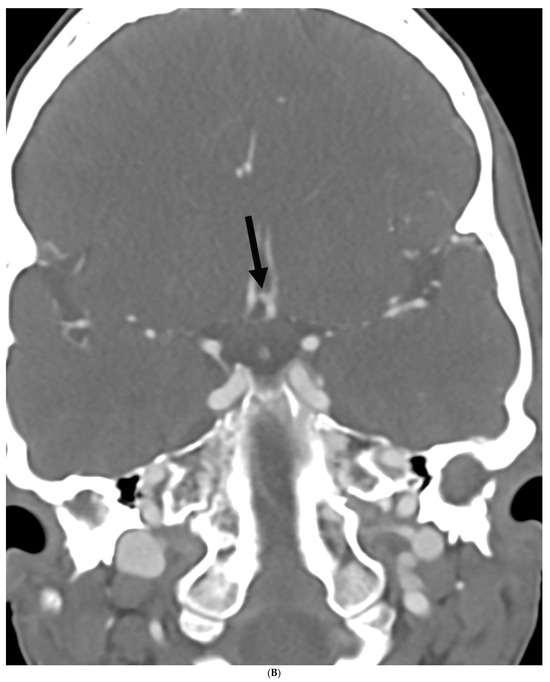

Prevalence of Intracranial and Cervical Artery Abnormalities in Patients with Hypermobile Ehlers–Danlos Syndrome and Hypermobility Spectrum Disorders Presenting to an Academic Headache Clinic

by Todd D. Rozen, Katelyn A. Bruno, Ethan M. Rozen, Frances C. Wilson, Marysia S. Tweet, Raymond C. Shields, Sharonne N. Hayes, Dacre R. T. Knight, Shilpa N. Gajarawala, Sukhwinder J. S. Sandhu, Alok A. Bhatt and DeLisa Fairweather

Neurol. Int. 2026, 18(2), 33; https://doi.org/10.3390/neurolint18020033 - 11 Feb 2026

Background/Objective: It remains unknown whether patients with the more common forms of hypermobility carry an elevated risk for the development of intracranial/cervical artery abnormalities. The objective of this study was to determine the prevalence of unruptured intracranial aneurysms, spontaneous cervical artery dissections, and fibromuscular dysplasia in patients with hypermobile Ehlers–Danlos Syndrome (hEDS) and hypermobility spectrum disorders (HSD) who presented to an academic headache clinic. Methods: This is a retrospective cohort study. We used an electronic medical record to look for all patients seen at the Mayo Clinic Florida Headache Center and EDS Clinic between 2019 and 2025 with a diagnosis of hEDS or HSD and neuroimaging of both the intracranial and cervical arteries. Results: There were 103 patients who met the inclusion criteria. There was no statistically significant difference between hEDS and HSD patients in developing cerebral/cervical arterial anomalies. Of the sample, 95% of the hypermobile patients with abnormal neuroimaging also had migraine. A total of eleven (10.7%) patients (hEDS + HSD) were diagnosed with unruptured intracranial aneurysms. Trends included age less than 50 years, small aneurysms in the anterior circulation, and having migraine with aura. Five (4.8%) patients were diagnosed with spontaneous cervical artery dissection with trends for HSD, over the age of 50 years, vertebral artery involvement and a history of migraine without aura. Six (5.8%) patients were diagnosed with fibromuscular dysplasia with trends for HSD, over the age of 50 years, carotid artery involvement and a history of migraine with aura. Conclusions: This is the first study to identify that patients with the more common type of EDS, HSD and hEDS, and a possible concomitant history of migraine have a heightened risk for the development of unruptured intracranial aneurysms, spontaneous cervical artery dissections, and fibromuscular dysplasia. Our findings suggest the need for targeted screening with intracranial and extracranial arterial imaging for this unique patient population. Full article

Figure 1